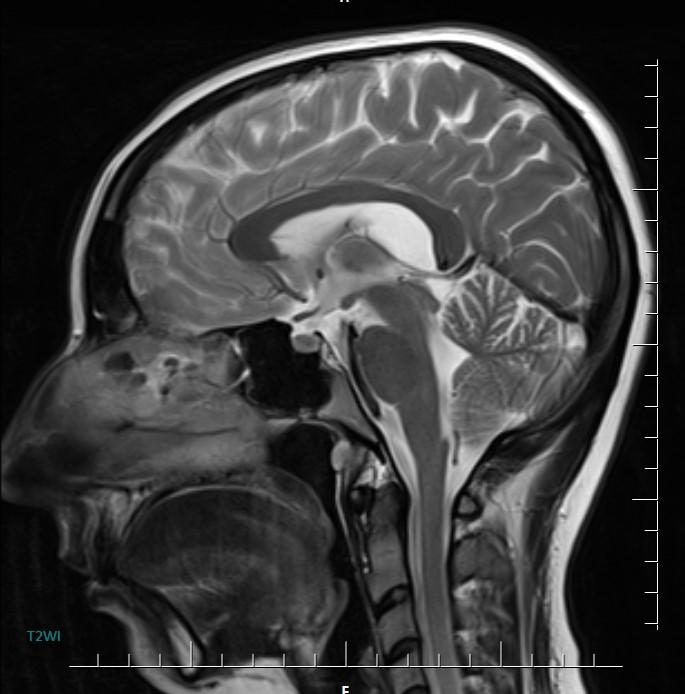

MR images incidentally revealed a triangular-shaped CSF space between the lateral ventricles (arrows).

In the brain, the cavum velum interpositum is a condition where there is a dilated cerebrospinal fluid (CSF) space involving the cistern of the velum interpositum. It usually occurs in newborns.

Axial MR/CT image shows a triangular-shaped CSF space situated behind the foramen of Monro, between the lateral ventricles. Coronal image demonstrates the elevated and splayed fornices.